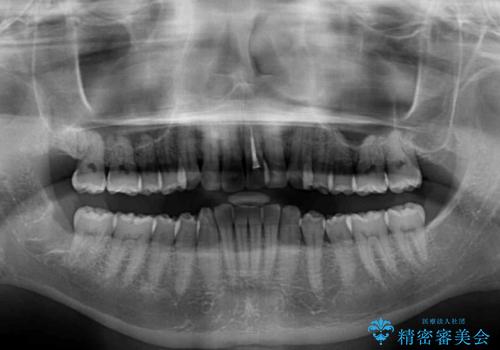

- 前歯のデコボコを治したいとのことで来院された患者様です。

上下顎ともに歯列全体の後方移動とIPR(歯と歯の間を削る)によってデコボコが解消するように設計し、インビザラインにより治療を行うこととしました。